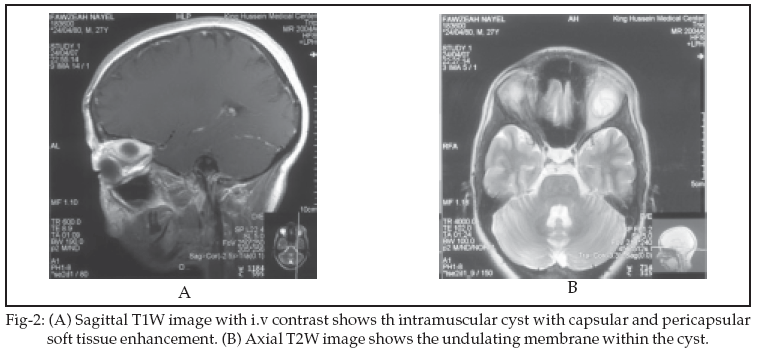

Orbital MRI was done which showed a 2 X 2cm well circumscribed, cystic lesion located solely in the superior rectus muscle. It appeared hypointense in T1W (Figure-1A) and hyperintense in T2W images with internal undulating hypointense membrane (Figure-2B). The internal undulating hypointense membrane is the characteristic appearance of hydatid cyst anywhere in the body. Following I.V contrast injection, the cyst showed thick enhancement of the capsule (Figure-1B, Figure-2A). The patient underwent surgical removal of the cyst by transcranial surgical approach. Post operative examination revealed no proptosis, residual limitation of upgaze occular movement. Postoperative MRI shows no evident of cyst residue.

The main clinical feature of the disease is progressive unilateral proptosis. Other clinical findings include mechanical restriction of occular movements, visual impairment, occular tension or pain, lid edema, papilloedema, and optic atrophy.7,8,12 Upon MRI examination, the cystic lesion appeared low signal on T1W images, high signal on T2W images, capsular and pericapsular soft tissue enhencement, and the capsule was seen as a hypointense rim surrounding the mass on T2W images. Those features were also reported in previous cases.4,5 However, we have also detected an undulating membrane within the hydatid cyst which represent a typical characteristic of the echinococcal cysts in other organs.